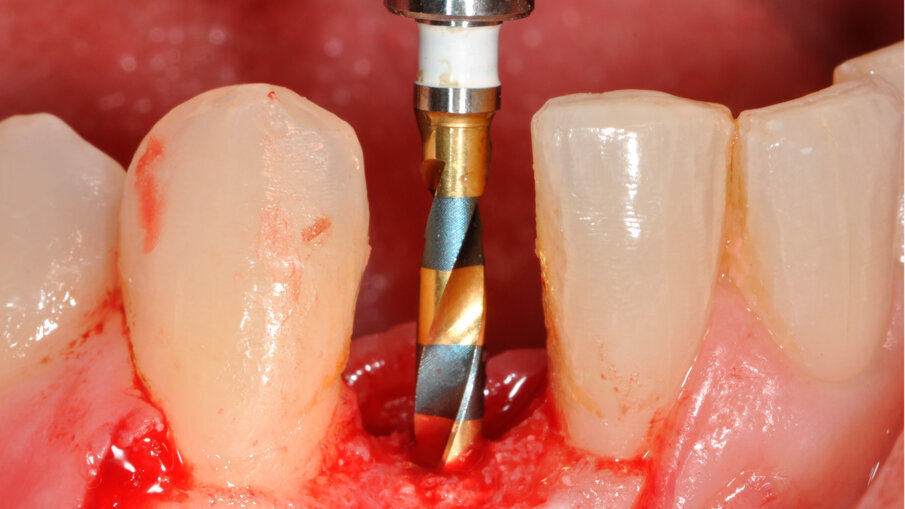

V rámci prvního kroku zavádění implantátu byly pomocí chirurgické šablony vyhodnoceny biologické aspekty podle pravidla 3A-2B (obr. 3). První pozice pro vrtání byla vyznačena tak, aby bylo dosaženo 2B a zajištěn úhel osteotomie pomocí vrtáku Precision Drill EV (Dentsply Sirona). Úhel byl potvrzen a osteotomie v hloubce pro implantát byla preparována pomocí vrtáku Twist Drill EV (Dentsply Sirona; obr. 4). Hloubka osteotomie byla zkontrolována pomocí nástroje Implant Depth Gauge EV (Dentsply Sirona (obr. 5). Poté byl zaveden implantát OsseoSpeed EV 3.6 o délce 11 mm (obr. 6). Předpokladem bylo, že zbývající aproximální kost poskytne oporu aproximální papile. Periapikální RTG snímek pořízený bezprostředně po zavedení implantátu potvrdil, že implantát není v kontaktu s žádným ze sousedních kořenů (obr. 7). Poté byl za použití otiskovací kapny Implant Pick-up Design EV (Dentsply Sirona), což je samonaváděcí otiskovací komponenta, která se umisťuje do implantátu, pořízen otisk, jehož účelem bylo získání informací o pozici implantátu (obr. 8). Provizorní abutment Temporary Abutment EV byl upraven v oblasti krčku tak, aby se zabránilo kontaktu s aproximální kostí a bylo možné správné dosednutí (obr. 9). Za použití kofferdamu pak byla pryskyřicí ihned upevněna provizorní náhrada (obr. 10). Poté byla náhrada sejmuta, dokončena, vyleštěna a za lehkého přitlačení opět nasazena.